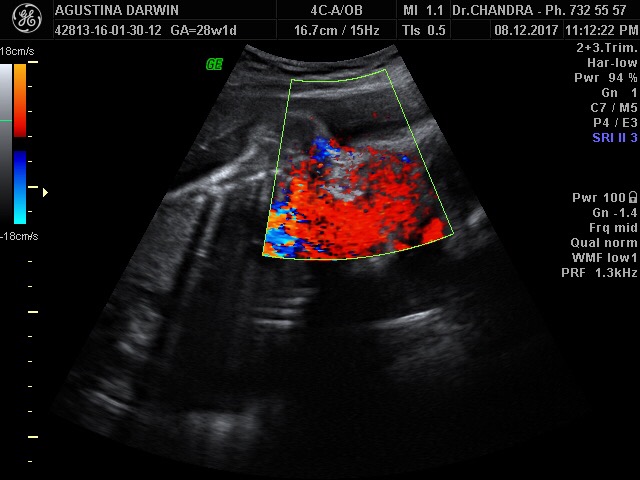

Dan langsung ditemui,plasenta / ari2nya melilit di lehernya, tapi untungnya lilitannya hanya 1x, longgar dan tidak erat. Pada usia kehamilan 24w, masih besar kemungkinan janin bisa melepaskan sendiri lilitannya.. tapi tidak menutup kemungkinan,janin bisa terlilit lebih banyak lilitan. Lalu diperiksa aliran darah di tali plasenta tersebut, Puji Tuhan alirannya bagus

| ini gambaran lilitan tali pusat dengan menggunakan doppler usg warna |

Berat dd sekarang 1.235gram,. lebih besar sekitar 180gram dari usianya,. tapi masih tergolong normal.. Detak jantung, aliran darah, resiko preeklampsia juga rendah.. Puji Tuhan hasilnya semua baik..